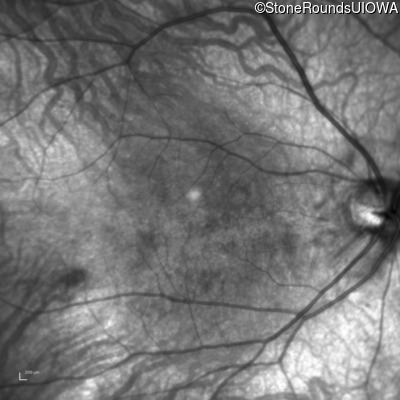

Infrared Fundus Photograph - Left - 20/100

Exemplar